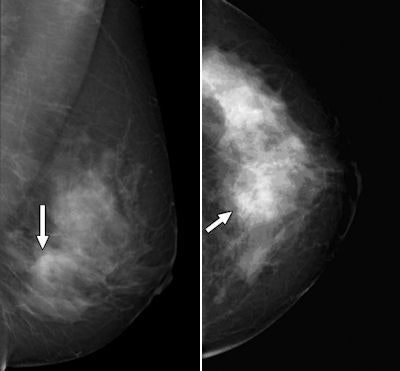

| Forty-eight-year-old woman with palpable lesion in right upper breast found by her physician. Mediolateral oblique (left) and craniocaudal (right) mammograms. Patient did not feel lump, and a BB marker was not placed at time of her mammogram. Images were originally interpreted as showing no evidence of suspicious lesion. However, retrospectively, possible asymmetries and architectural distortions may be present centrally (arrows). Fig 1a, b. Godinez J, Gombos EC, Chikarmane SA, Griffin GK, Birdwell RL. AJR. 2008;191(1):272-277. All images courtesy of the American Roentgen Ray Society. |